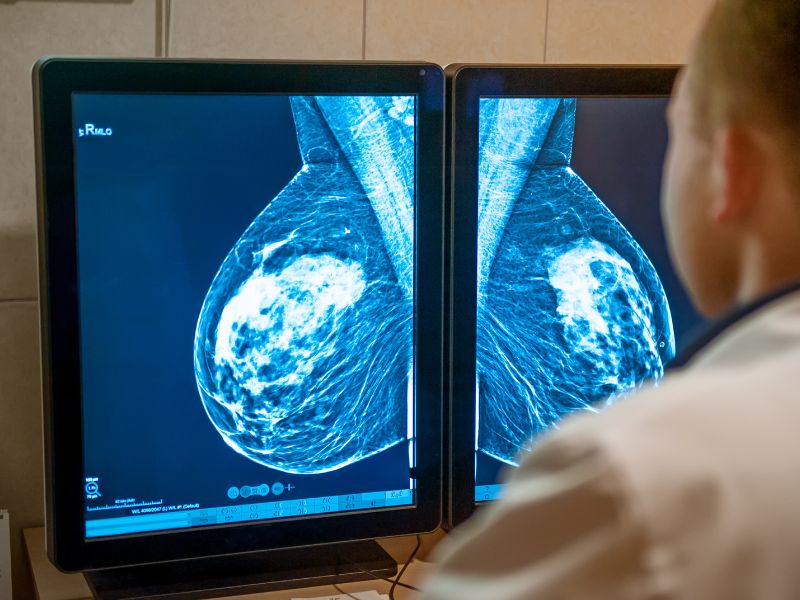

Gustoću dojke ne možete osjetiti. To se odnosi na količinu masti u odnosu na količinu gušćeg tkiva poput žlijezda i kanala. Mamografija je jedini način da saznate stupanj gustoće svojih dojki. Gustoća dojke varira, a genetski faktori mogu utjecati na to. Također se mijenja tijekom života. S godinama dojke obično postaju manje guste, odnosno imaju više masti, a manje žlijezda i kanala.

Ako imate guste dojke, to može otežati otkrivanje potencijalnih abnormalnosti na mamografiji. Visoka gustoća dojki može također povećati rizik od razvoja raka dojke, stoga je važno da redovito obavljate preglede i pratite upute svojeg liječnika.